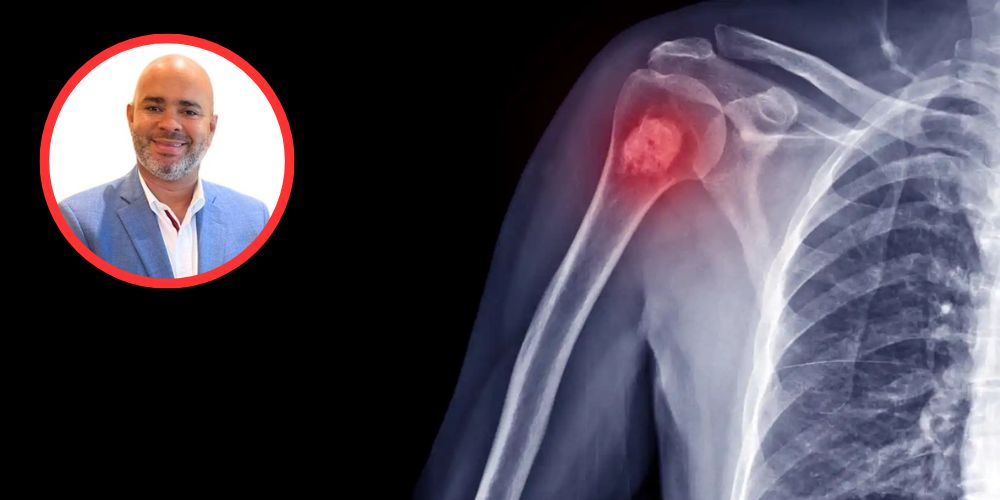

Santo Domingo.- El volumen de pacientes con actividad neoplásica con tumores a nivel óseo, articular y partes blandas ha aumentado significativamente en la República Dominicana, según lo afirman los médicos ortopedas traumatólogos Andy de León y Edwin Suffront.

“Estamos viendo semanalmente más de cinco casos de patologías Oseas tumorales, esto en comparación de los casos vistos antes del covid, por lo que se registra un aumento significativo y debemos tomar en consideración estas estadísticas lo que nos ha motivado a iniciar una investigación”, señaló el especialista.

El principal síntoma, que motiva a los pacientes ir a una consulta, es el dolor, según explican los especialistas, ya que los medicamentos dejan de hacerle efecto o empiezan a cojear o dolerle las articulaciones, así como se presenta un aumento del área anatómica.

Los médicos ortopedas traumatólogos de los centros Trauma Care y Hospiten, realizaron durante el fin de semana una cirugía en el país, en la que extirparon un gran tumor de células gigantes con un comportamiento de malignidad de la tibia proximal.

Una vez realizada la intervención quirúrgica, donde extirparon el tumor de rodilla completa, colocaron al paciente una prótesis modular tumoral.

Explicaron, que la prótesis modular permite evitar la amputación, preservando la función de la extremidad, que a su vez puede mejorar la movilidad y la calidad de vida del paciente, permitiéndole realizar actividades diarias.

“Hicimos una recesión del fémur distal hasta la tibia, procedimiento que se extendió por siete horas”, añadió De León.

De igual forma, el especialista en trauma, dijo que para realizar el procedimiento quirúrgico fue necesario disecar los vasos, los nervios de la extremidad inferior del paciente, para poder mantener con viabilidad el miembro inferior derecho del paciente.

“Se colocó una prótesis modular tumoral que alberga una fijación a nivel del fémur, una bisagra que va a ser a su vez de rodilla y una implementación de varios módulos para conformar lo que es la tibia y una fijación intramedular, luego se hizo una reconstrucción, el paciente se encuentra en buenas condiciones de salud y este es un procedimiento que permite que el paciente conserve su miembro que tenga la funcionalidad de la prótesis y le permita realizar sus actividades tanto física como laborales y deportivas, que es la finalidad de los médicos, devolverle sus funcionalidades al paciente”, puntualizó.